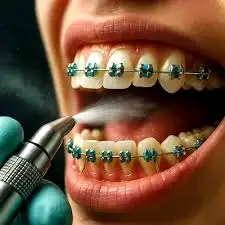

درمان ارتودنسی یکی از بهترین روشها برای رسیدن به لبخندی زیبا و دندانهایی منظم است، اما همزمان با مزایای فراوان آن، احتمال تجمع پلاک، جرم و ایجاد پوسیدگی نیز بیشتر میشود. براکتها و سیمها اگرچه در راستای اصلاح ناهنجاریها به کار میروند، اما فضای مناسبی برای گیر غذایی، رشد باکتریها و ایجاد لکههای سفید (White Spot) فراهم میکنند. به همین دلیل، جرمگیری منظم و فلورایدتراپی دورهای در طول ارتودنسی نقشی حیاتی در حفظ سلامت دندانها دارند.

وجود براکتها، سیمها و الاستیکها باعث میشود سطوح بیشتری در دهان برای گیر غذایی ایجاد شود. مسواکزدن در اطراف براکتها دشوارتر است و حتی با رعایت بهداشت متوسط نیز پلاک بیشتری روی دندان باقی میماند. این پلاک میتواند در مدت کوتاهی تبدیل به جرم سختشده شود.

یکی از بدترین عوارض ارتودنسی، لکههای سفید (White Spot) یا شروع پوسیدگی مینای دندان است. این لکهها دقیقاً کنار براکتها ظاهر میشوند و دائمی هستند.

فلورایدتراپی شامل استفاده از ژل یا وارنیشهای حاوی فلوراید با غلظت بالا است که توسط دندانپزشک روی دندانها قرار میگیرد.

7. آیا جرمگیری حین ارتودنسی به براکتها آسیب میزند؟

خیر؛ تکنیکهای جرمگیری مدرن و دستگاههای اولتراسونیک کاملاً ایمن هستند و براکتها را شل نمیکنند.

جرمگیری حتی به کاهش التهاب اطراف براکت کمک میکند و درمان را بهتر پیش میبرد.